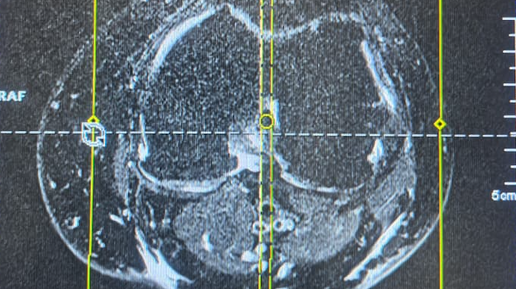

Высокопольный томограф с напряженностью магнитного поля 3 Тесла позволяет получать изображения с более четким разрешением для повышения точности и качества диагностики. Использование такого оборудования позволяет увидеть самые минимальные изменения в головном мозге, что особенно важно для проведения исследований при рассеянном склерозе, опухолях, болезни Альцгеймера и эпилепсии. Еще одно важное преимущество этого томографа — высочайшая эффективность при постановке диагнозов в ортопедии. Он делает снимки...